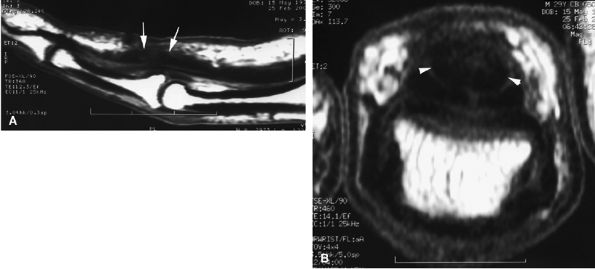

FIGURE 11.45 ● Open partial laceration of the flexor pollicis longus tendon. Sagittal (A), coronal (B), and axial (C) post-enhanced fat-suppressed T1-weighted images showing focal intratendinous high signal with conservation of a thin lateral continuity (arrow). Single orthogonal plane images may be misleading, and a partial tear may be mistaken for a complete tear. This potential pitfall is well demonstrated on the sagittal image (A).